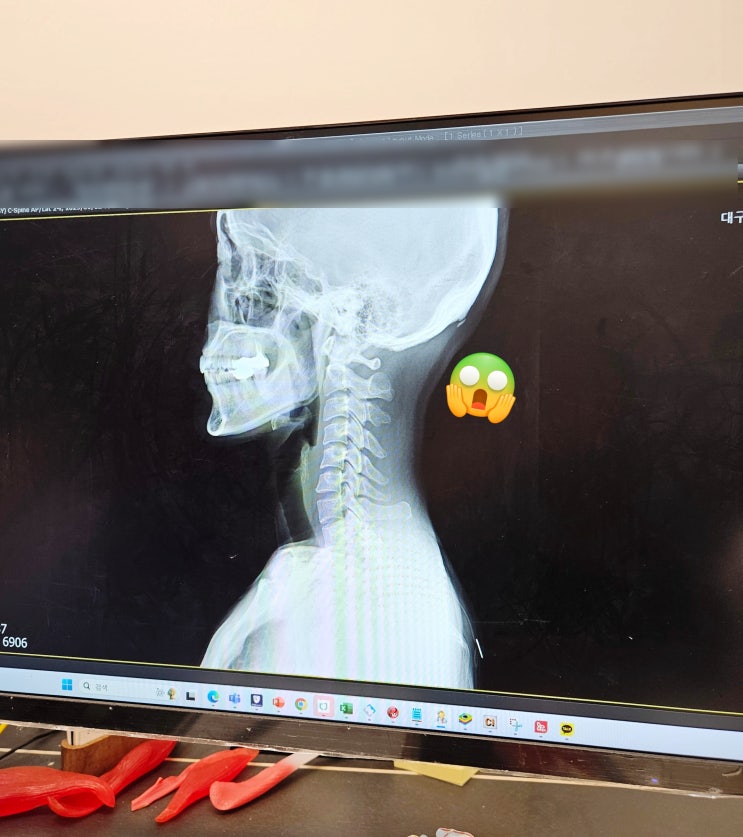

대구 수성구정형외과 삼성글로벌정형외과 :) 일자목 도수치료받고왔어용ㅎ

사무직이라 목이랑 어깨가 한번씩 안좋아서 고민이었는데요~ 주말에 잠을 잘못잤나? 목이 너무 뻣뻣해서 고...